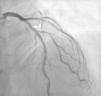

On March 12, 2016, the patient was readmitted to the hospital due to an episode of NSTEMI. He underwent another catheterization procedure around 12 hours after admission, which showed normal patency of the previously treated vessels with no signs of restenosis in the stents previously implanted. A new severe sub-occlusive lesion with abundant thrombotic material was found in the left anterior descending (LAD) artery. A lesion with a lumen reduction of about 30% was also identified in the same segment (Figure 2). Intracoronary nitrate administration ruled out vasospasm. Angioplasty of this new lesion was performed during the same procedure, with implantation of a drug-eluting stent. Abciximab was used as supplemental antithrombotic therapy. In the hours following the procedure, a peak troponin value of 0.30 pg/ml (normal value <0.04 pg/ml), a peak BNP value of 59 mg/ml and a peak CRP value of 18.6 mg/l (normal value <5.0) were recorded. Thyroid function was normal and thrombophilia testing was negative. The patient remained electrically and hemodynamically stable, maintaining sinus rhythm at all times. He was discharged three days later with instructions to increase to atorvastatin dose to 80 mg. The other outpatient medication remained unchanged. The echocardiography performed prior to discharge was comparable to the previous one, with no new alterations in motility and no deterioration of ventricular function.